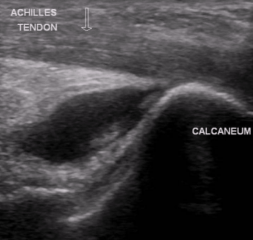

Achilles tendon

Strongest and thickest tendon in the body

Attachments

Proximal - gastrocnemius and soleus muscles

Distal - calcaneus (heel bone)

Retrocalcaneal bursitis

Partial or complete Achilles tendon tears